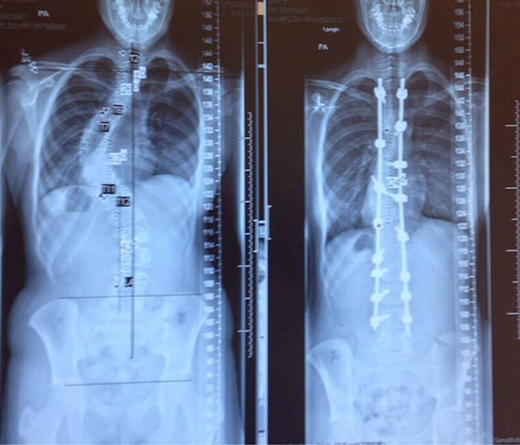

Tấm phim chụp trước và sau khi điều trị chứng vẹo cột sống.